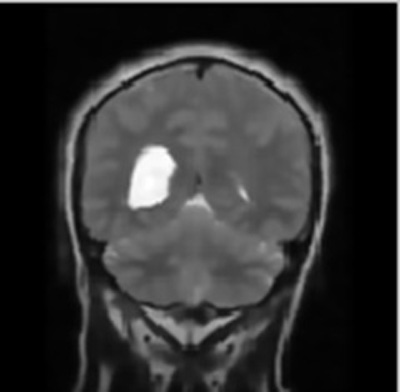

To check functionality of the proposed work for the detection of brain cancer in MRI images using HMM classifier, a set of 6 images was obtained from BITE database. All images were processed to extract cancerous portion using HMM (Hidden Markov Model) classifier and then the corresponding parameters such as accuracy, Mean Square Error (MSE), Peak Signal- to- Noise Ratio (PSNR) and fault rate dust detection were calculated for detection using the HMM classifier. So when the code was run and an appropriate image was selected for the intended task of cancer detection and extraction of the abnormal portion, the first output was the figure showing input MRI image and the corresponding filtered image using subplot command to display them at position (1, 2, 1) and (1, 2, 2) respectively.

The respective filtering output is shown in Fig. (2).